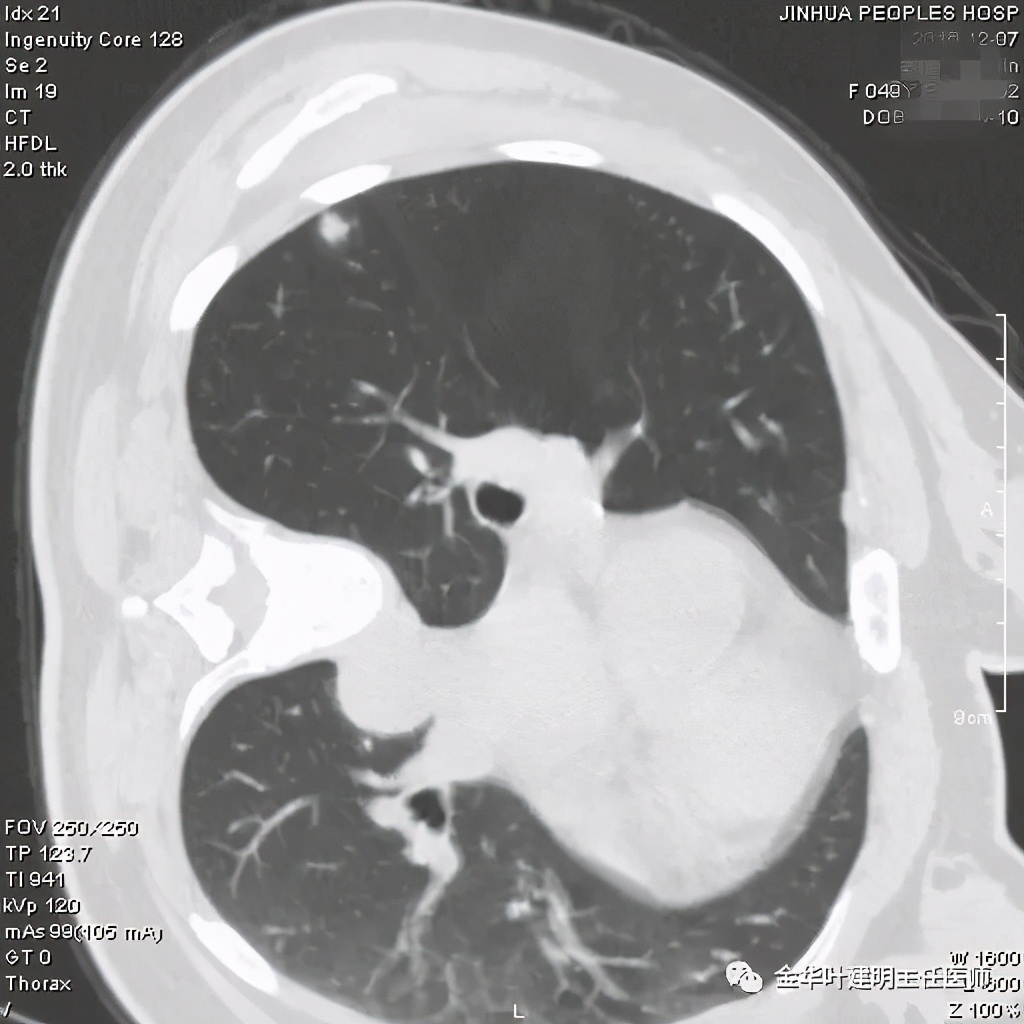

医生考虑炎性可能性大,予以头孢美唑抗炎治疗10来天,之后约一个月后复查了靶扫描,图像如下:

实性部分我看是有所缩小改善的,边上磨玻璃样的晕征更加明显了点

上图示病灶边缘向内凹陷,同时仍伴晕征

上图红色箭头示仍有血管进入,但蓝色箭头示边缘内凹,绿色示仍有晕征

上图红色箭头示血管进入病灶